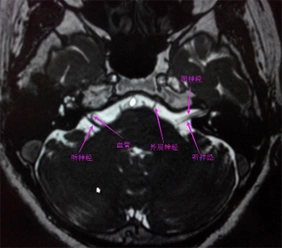

三叉神经(痛),面神经面肌痉挛血管磁共振成像mrta技术 - 好大夫在线